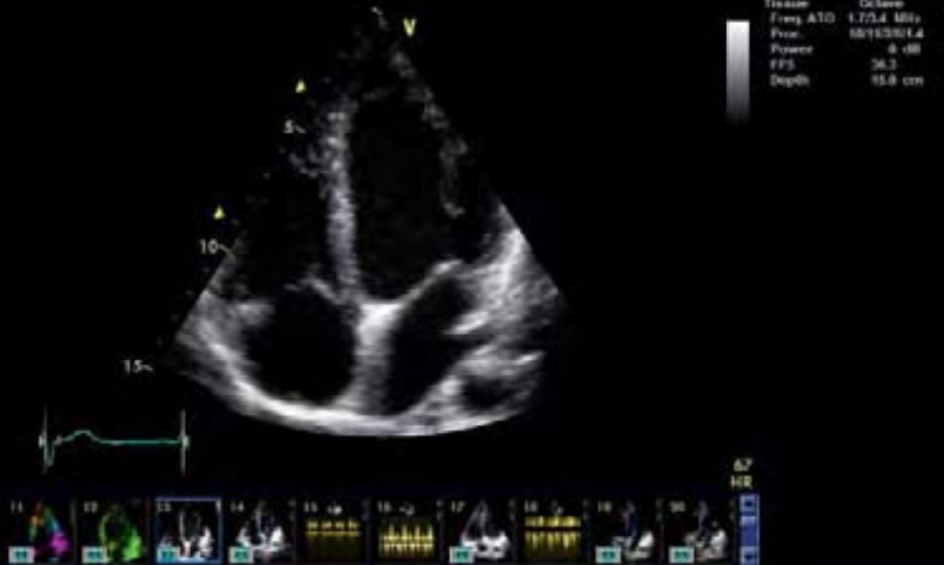

- Análisis y detallado informe de todos los datos vitales del sistema cardiovascular.

- Vivid S6 permite al médico realizar estudios de variadas especialidades, vascular, abdominal, pediátrico, fetal, obstetricia y quirófano.